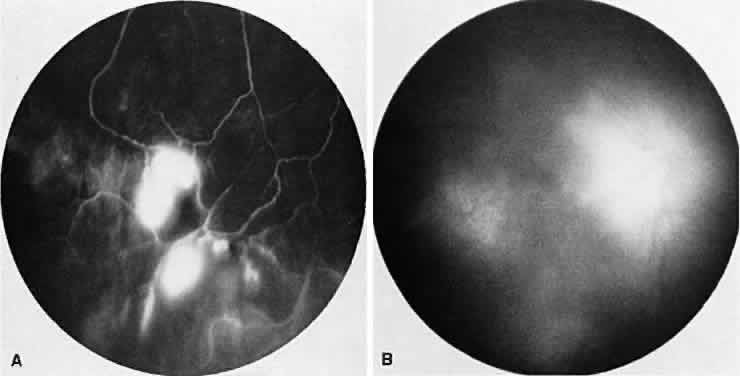

SARCOIDOSIS

Sarcoidosis is a systemic, idiopathic, noncaseating, granulomatous disease that affects various organs, including the eye, brain, lung, and skin. Ocular findings may include conjunctival nodules; anterior iridocyclitis; vitreous cells; retinal, optic nerve, and choroidal granulomas (Fig. 7A); retinal vasculitis (venules are preferentially affected); cystoid macular edema; retinal vessel occlusion; and disc and retinal neovascularization.

Fig. 7. Sarcoidosis. A. Choroidal granuloma. B. Fluorescein angiogram shows staining of the choroidal granuloma.

The FA reflects the various clinical entities. Retinal venular walls stain, particularly where there are perivenular exudates.25–27 More extensive venous involvement can produce a picture of dilated veins and perivenous leakage.27 Peripheral neovascularization occurs near areas of retinal capillary nonperfusion.25,28 Optic disc granulomas and optic disc neovascularization both leak extensively (Fig. 8A); sarcoid retinal lesions also stain (see Fig. 7B).27 In disc edema, the disc is hyperfluorescent and leaks fluorescein (see Fig. 8B).25

Fig. 8. Sarcoidosis. A. Fluorescein angiography shows two separate areas of neovascularization of the peripheral retina. B. Extreme leakage of dye from the right disc with cystoid macular edema of the right macular region in a patient with chronic sarcoidosis.

Four main patterns can be identified with ICG angiography. The first and most common pattern is hypofluorescent dark spots in the early and intermediate phases of the angiogram. These spots either become isofluorescent or remain hypofluorescent in the late phases. The second pattern is focal hyperfluorescent spots seen in the intermediate and late phases. The third pattern is fuzzy choroidal vessels due to perivascular choroidal leakage in the intermediate phase. Finally, the fourth pattern is characterized by diffuse zonal hyperfluorescence representing choroidal staining in the late phase of the angiogram. The latter two patterns resolved after systemic corticosteroid treatment.29